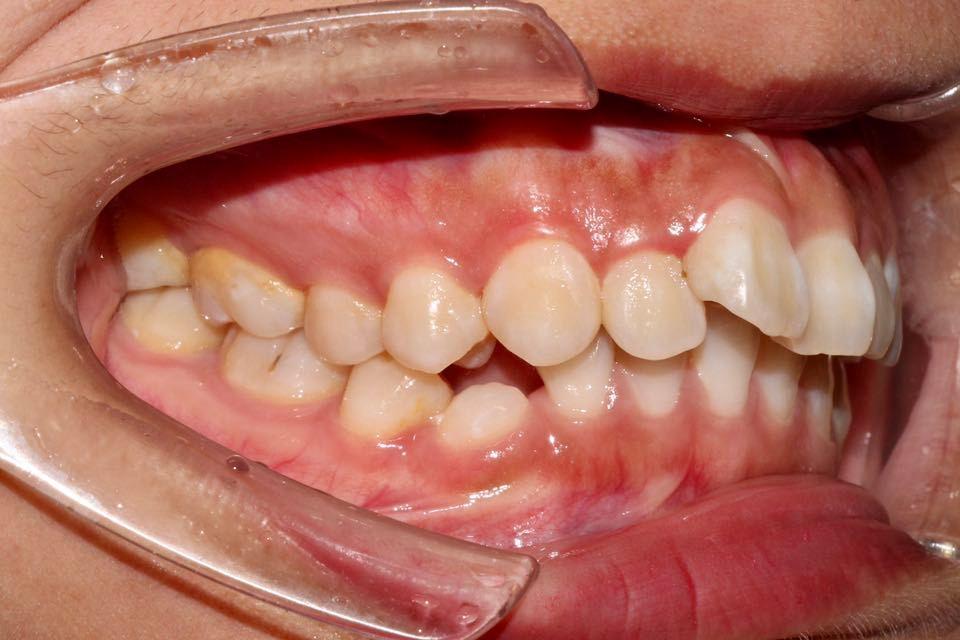

牙性齙牙和骨性齙牙的區(qū)別

二、牙性齙牙和骨性齙牙的區(qū)別

外觀表現(xiàn)

牙性齙牙:通常只是牙齒向前突出,唇部軟組織形態(tài)相對(duì)正常,側(cè)面看起來(lái)主要是牙齒的問(wèn)題。

骨性齙牙:除了牙齒前突,還伴有上頜骨的前突、下巴后縮等頜面骨的不協(xié)調(diào),唇部形態(tài)顯得更加突出,整個(gè)面部側(cè)面輪廓不美觀。